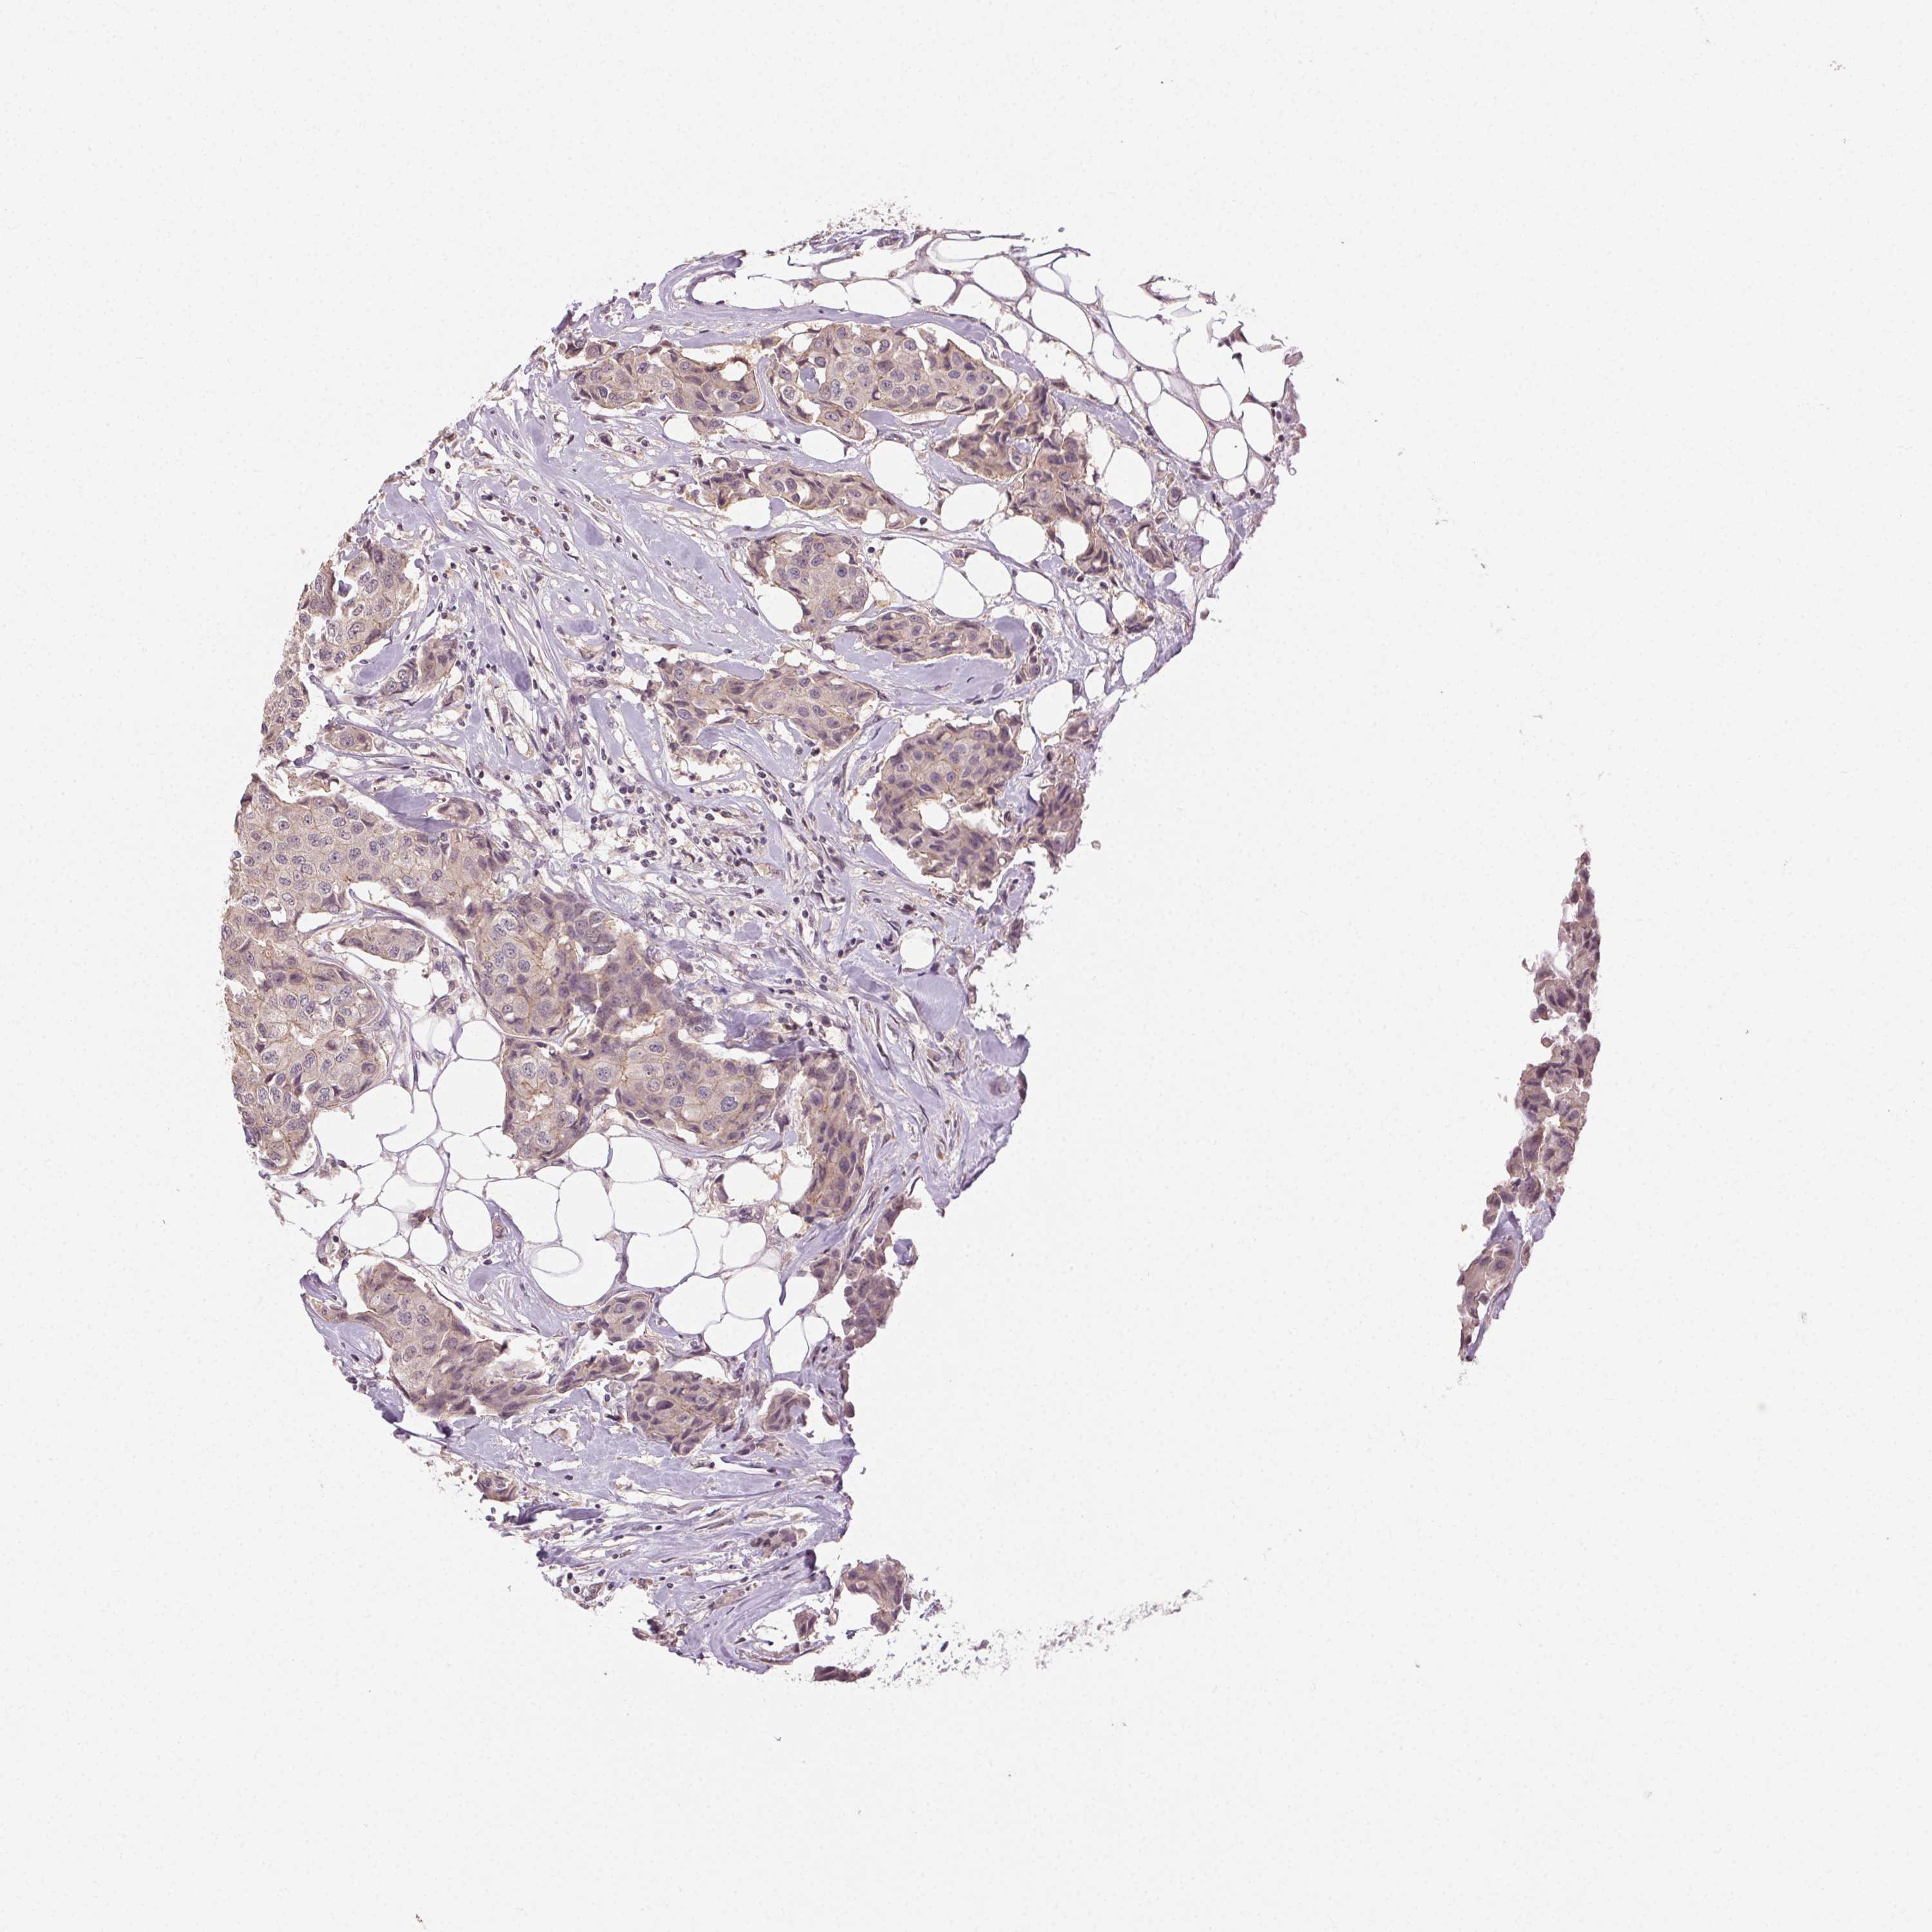

CANCER BREAST CANCER Show tissue menu

BRCA TCGA BRCA VALIDATION PROTEIN EXPRESSION

Breast cancer

Human cancer

Breast invasive carcinoma